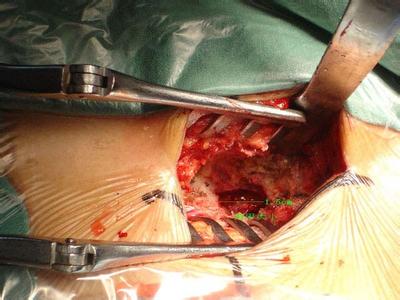

手术虽可切除骨刺,但仅限于骨赘过大或因关节常被“卡死”,经保守治疗无效者,或出现关节严重疼痛、畸形、关节不稳定、屈曲挛缩和严重肌萎缩者。这时可选择手术切除骨刺或关节鼠摘除术、关节成形术、关节融合术或人工关节置换术。但手术本身也是一种创伤,有些患者会因此造成无菌性炎症,而刺激骨质增生,甚至增生得更快。